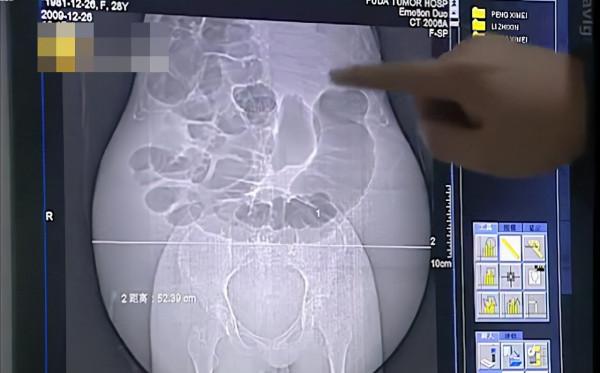

細妹加上肚子已經有160多斤重,可是醫生卻說是就連懷個五胞胎的肚子都沒有這麼大。而且根據醫生分析,細妹的肚子已經有五十斤重,腹圍也有100釐米左右,這樣的情況根本不正常。

可誰也沒想到,後面的事情更讓醫生震驚。醫生給細妹做了B超檢查,驚奇的發現細妹的肚子裡面全是液體,一點孩子的影子都沒發現。肚子裡面的液體還十分的渾濁,檢查的時候,就連內臟都看不清楚。

一個大活人,竟然在B超上面連個內臟都看不到,這怎麼可能呢?一個沒有五臟六腑的人還能活的下去?但是醫生轉念一想,B超儀器的超聲波只能穿透厚度為六七釐米的腹腔,可是細妹的肚子差不多能有五六十釐米厚了,所以醫生又建議細妹做CT檢查。

話說的簡單,細妹如果要做CT檢查可不是一件容易的事,因為CT儀器的這個孔,細妹的肚子是很難進去的。肚子的直徑已經遠遠超過了CT機設計的尺寸。可是再去做B超又沒有什麼意義,根本看不到肚子的內部情況。可是看在躺在病床上的細妹,臉色慘白,瘦弱的身體還要支撐著龐大的肚皮,醫生的內心一陣的難受。

醫生在商量治療方案的時候,發現只能先從細妹肚子裡的腹水著手,一天要放出5000毫升的腹水,十天就需要要抽出整整五萬毫升的液體,相當於要從細妹的身體裡取出100大瓶的啤酒啊。而只能抽乾液體,才能看到折磨細妹5年的“元兇”的真面目。